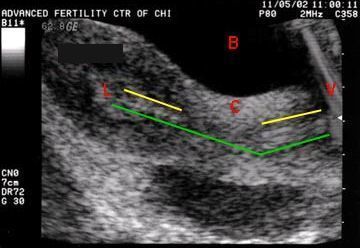

На рисунке 1 представлена УЗ-картина стимулированного яичника с множеством фолликулов. Красными точками помечен максимальный фолликул диаметром 18 мм:

Женщина спит и ничего не чувствует. На рисунке 1 показана ультразвуковая картина забора фолликулярной жидкости специальной иглой для получения созревших ооцитов.